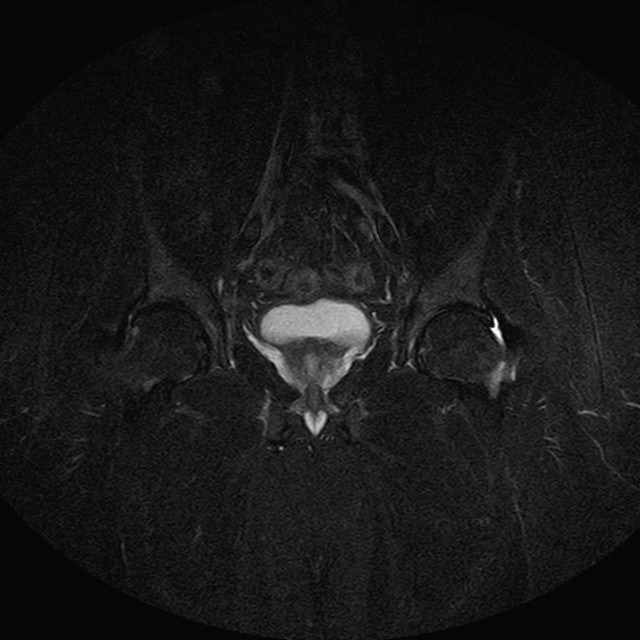

Esami: RMN BACINO

eSTIR

Evidenti e simmetriche alterazioni osteofitosiche in regione coxo femorale con riduzione delle rime articolari. Degenerazione completa del cercine glenoideo. Non attuali segni di versamento articolare. Non segni di edema osseo che escludono attuale algodistrofia od osteonecrosi. Lieve e simmetrica riduzione del trofismo della muscolatura glutea.